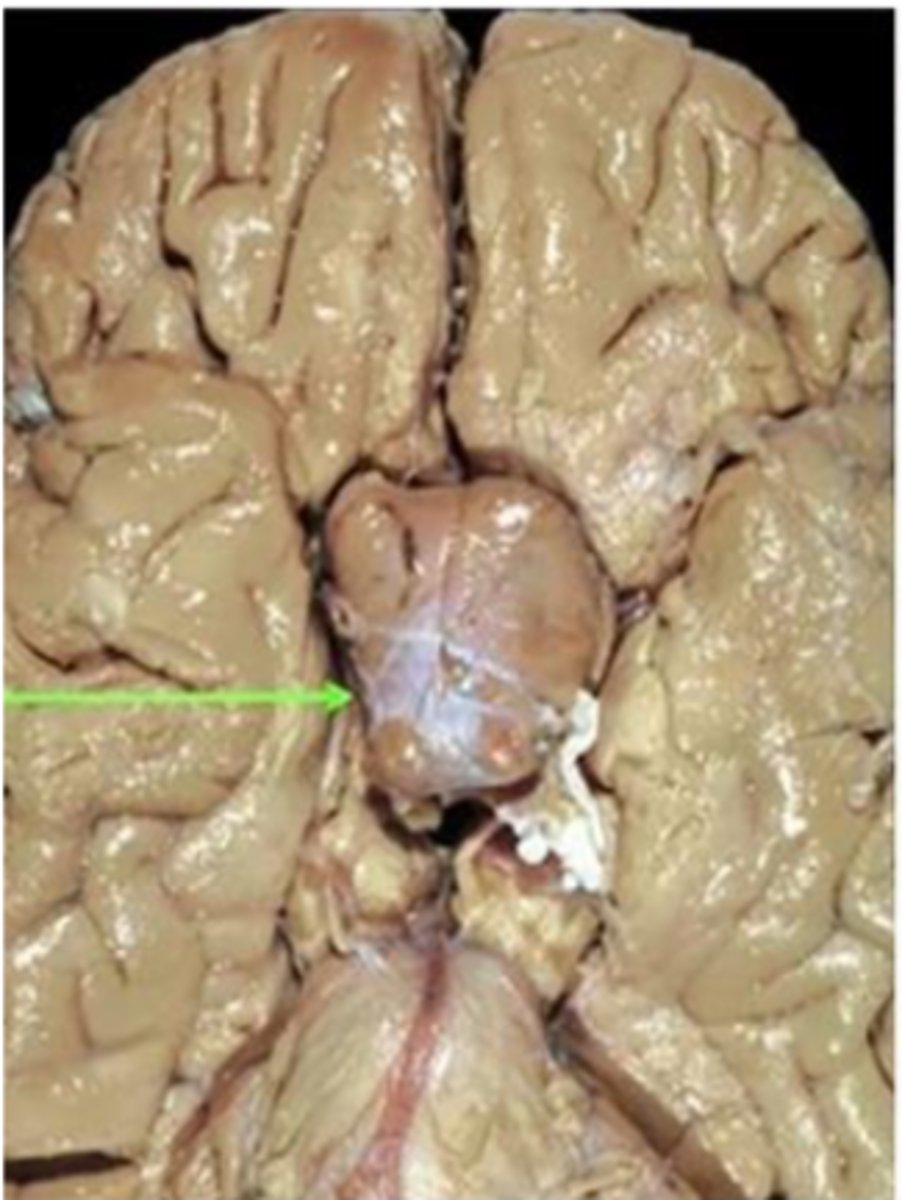

pituitary adenomas

-benign neoplasms of the anterior lobe of the pituitary gland

-extra-axial tumors (external to brain parenchyma)

most frequent primary intracranial neoplasm

30-50 years

avg age of presentation of pituitary adenomas

pituitary adenoma

gross pathology of _______ _________

-tan-to purple in color and creamy in texture

-macro or micro

histology of _______ _________

-uniform, polygonal cells arranged in thin cords and ribbons; monotonous appearance of small round cells

-see acidophils, basophils, and chromophobes